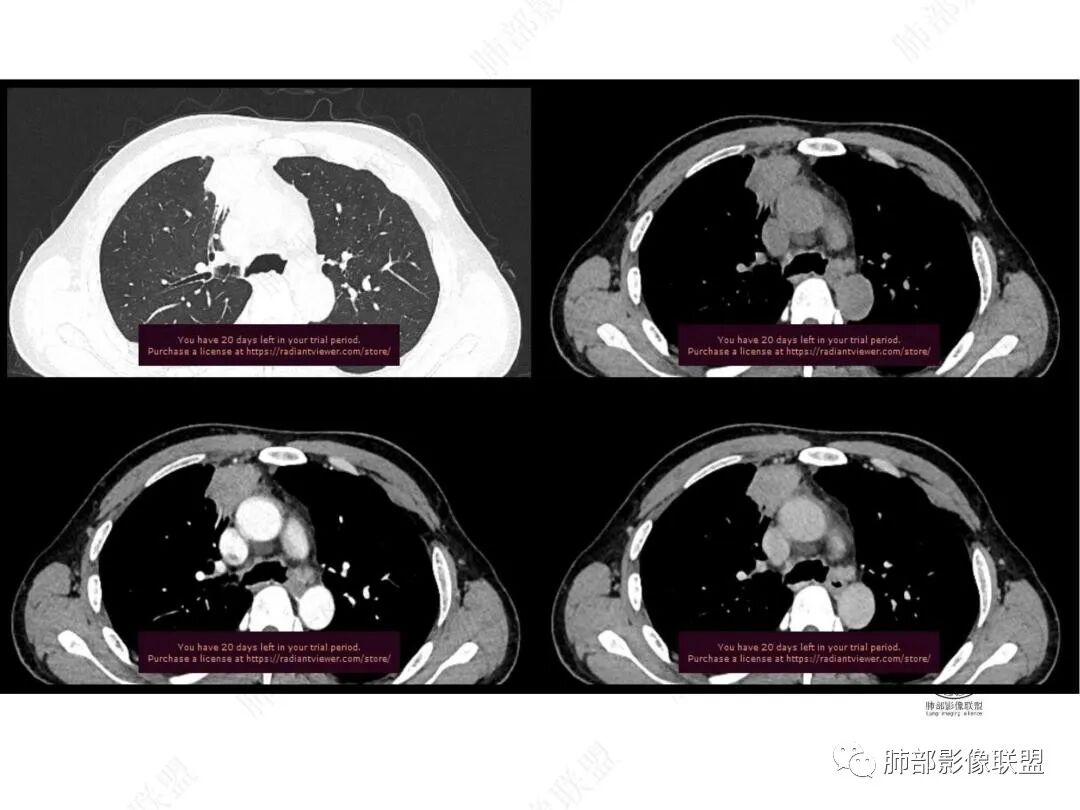

增强图像

中年男性,前纵膈旁团块,边缘平直,周围可见模糊的磨玻璃影,相邻支气管壁增厚,部分支气管进入病灶后阻塞,增强病灶渐进性强化,肝右叶见边缘不清的低密度影,增强渐进性强化。结合实验室检查,总体考虑炎性病变,自免性炎症?血管炎?

中年男性,右前纵隔旁不规则实变影,局部支气管进入后截断,病灶渐进性强化。肝脏右叶低密度灶,边界不清,呈明显渐进性强化。IMT?

男,49,低热3月。胸部CT:右肺上叶前段纵隔旁见团片影,部分边缘毛糙,部分平直、内收,邻近卫星灶、晕征,重建L征?支气管管壁增厚、进入后堵塞;纵隔可见肿大淋巴结;病灶密度较均匀,中度强化。肝脏片状低密度影,边缘模糊。考虑炎性病变,PC?TB?鉴别腺癌。

2.右肺上叶纵隔旁新发实性密度病灶,密度均匀,轻度强化,未见空洞、液化坏死及钙化,血管穿行自如,支气管进入后狭窄截止。灶周磨玻璃影边界不清,病灶未见明显分叶毛刺,平直、轻度收缩、周围偶见结节影,但未见树芽征。注意纵隔胸膜侵入或突入比较明确。纵隔淋巴结轻度增大。

4.肝脏病灶没有假包膜,没有动脉早期强化,没有肝硬化,未见扩张胆管,未见环形强化,也未显示靶征,缺乏肝细胞肝癌、胆管细胞癌、转移癌或肝脓肿特征。